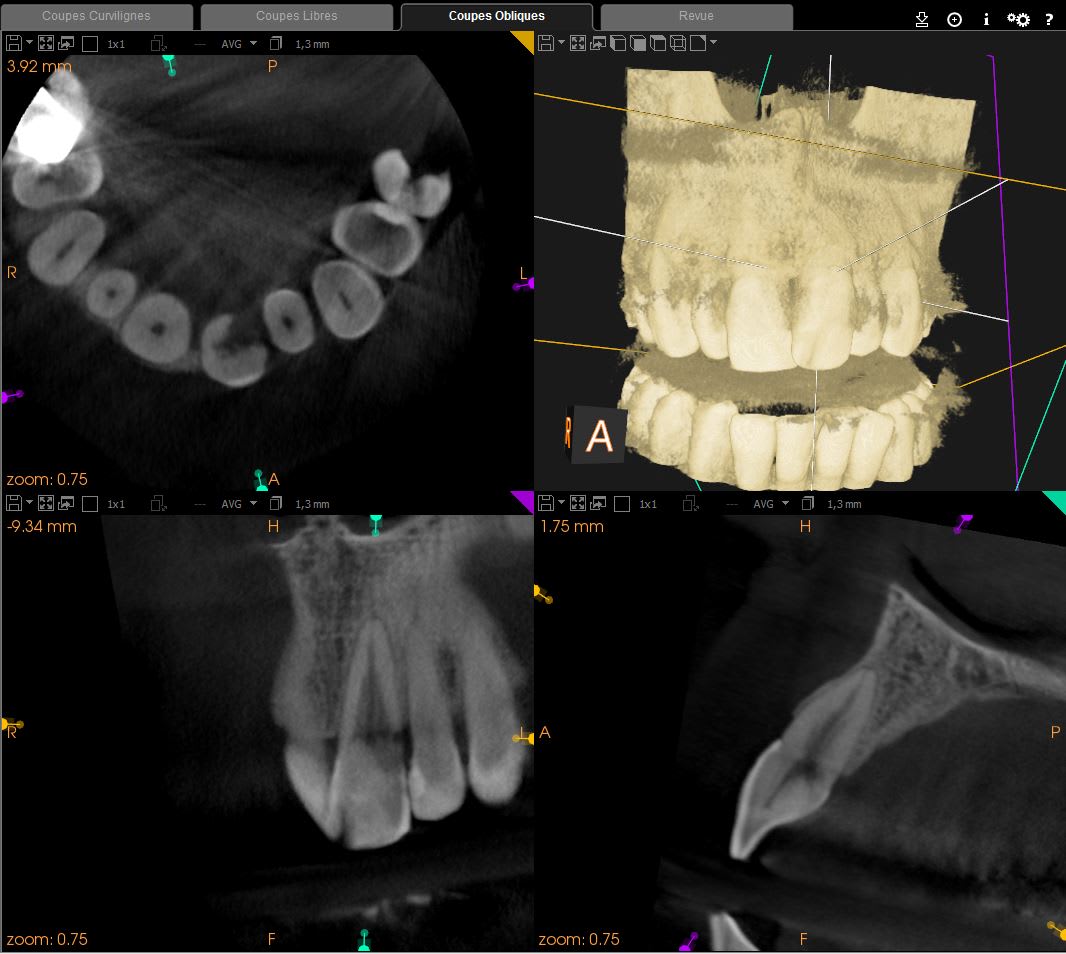

Un petit cas traité il y a 2 ans. La résorption s'étendait jusqu'à la limite du tiers apical et entourait complétement le canal.

Aux dernière nouvelles la dent est toujours là.

(Le point de départ est disto palatin, donc dur dur d'avoir une super belle limite pour l'obturation de la résorption)